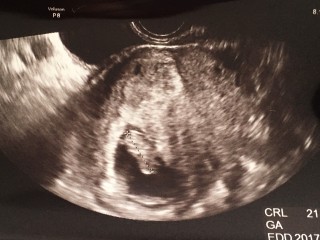

今日の検診で、予定日が決まりました(*^^*) 母子手帳も貰って来てねと先生の言葉を聞いて、凄く嬉しかったです(*^^*) CRL21.0mm 元気に成長してねo(^_^)o

赤ちゃん順調に育ってました! 二週間でかなり大きくなっていてビックリ!左下が頭で右上がおしりだそう。 帰りに母子手帳ももらってきました!